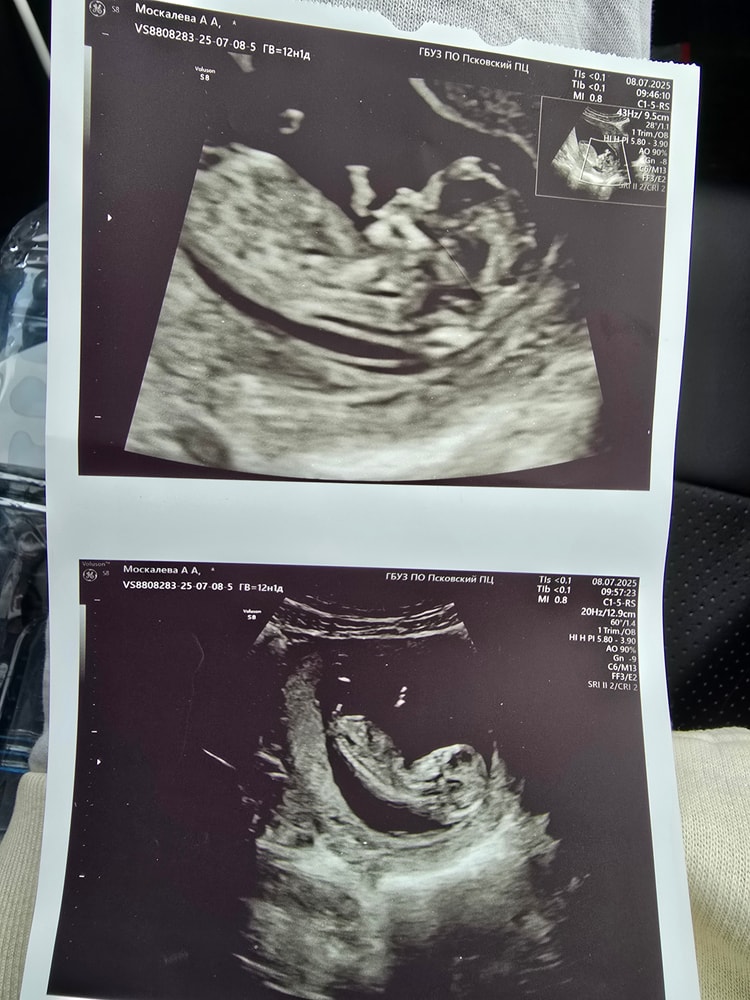

Наш первый скрининг ❤️

Обследования, узи, анализы